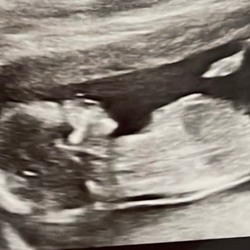

Ik heb 1 juni mijn spiraal er uit laten halen en nu bijna 6 weken zwanger. 1e ronde dus gelukt. Ik had al heel vroeg last van misselijkheid. Niet kotsmisselijk maar gewoon niet lekker. Ook had ik krampen in mijn buik en hele pijnlijke borsten. Allemaal kwaaltjes die ik tegen mijn menstruatie aan ook heb, maar dit was anderhalve week voor mijn NOD. Erg vroeg voor die kwalen dus. Iets in mij zei gewoon dat ik zwanger was. En dat bleek dus anderhalve week later ook zo te zijn🥰